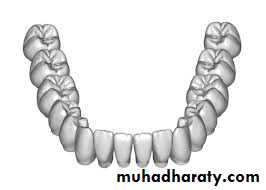

• Virtual Dental Models.

• Models of the teeth, the traditional diagnostic record from the beginning of orthodontics, have been used to view the relationships of the teeth from any orientation. The advent of digitized laser-scanned dental impressions that produce a three dimensional image of the teeth has overcome the problem of having to pour and trim plaster casts and has obviated the need to store and retrieve the models each time a patient is seen.